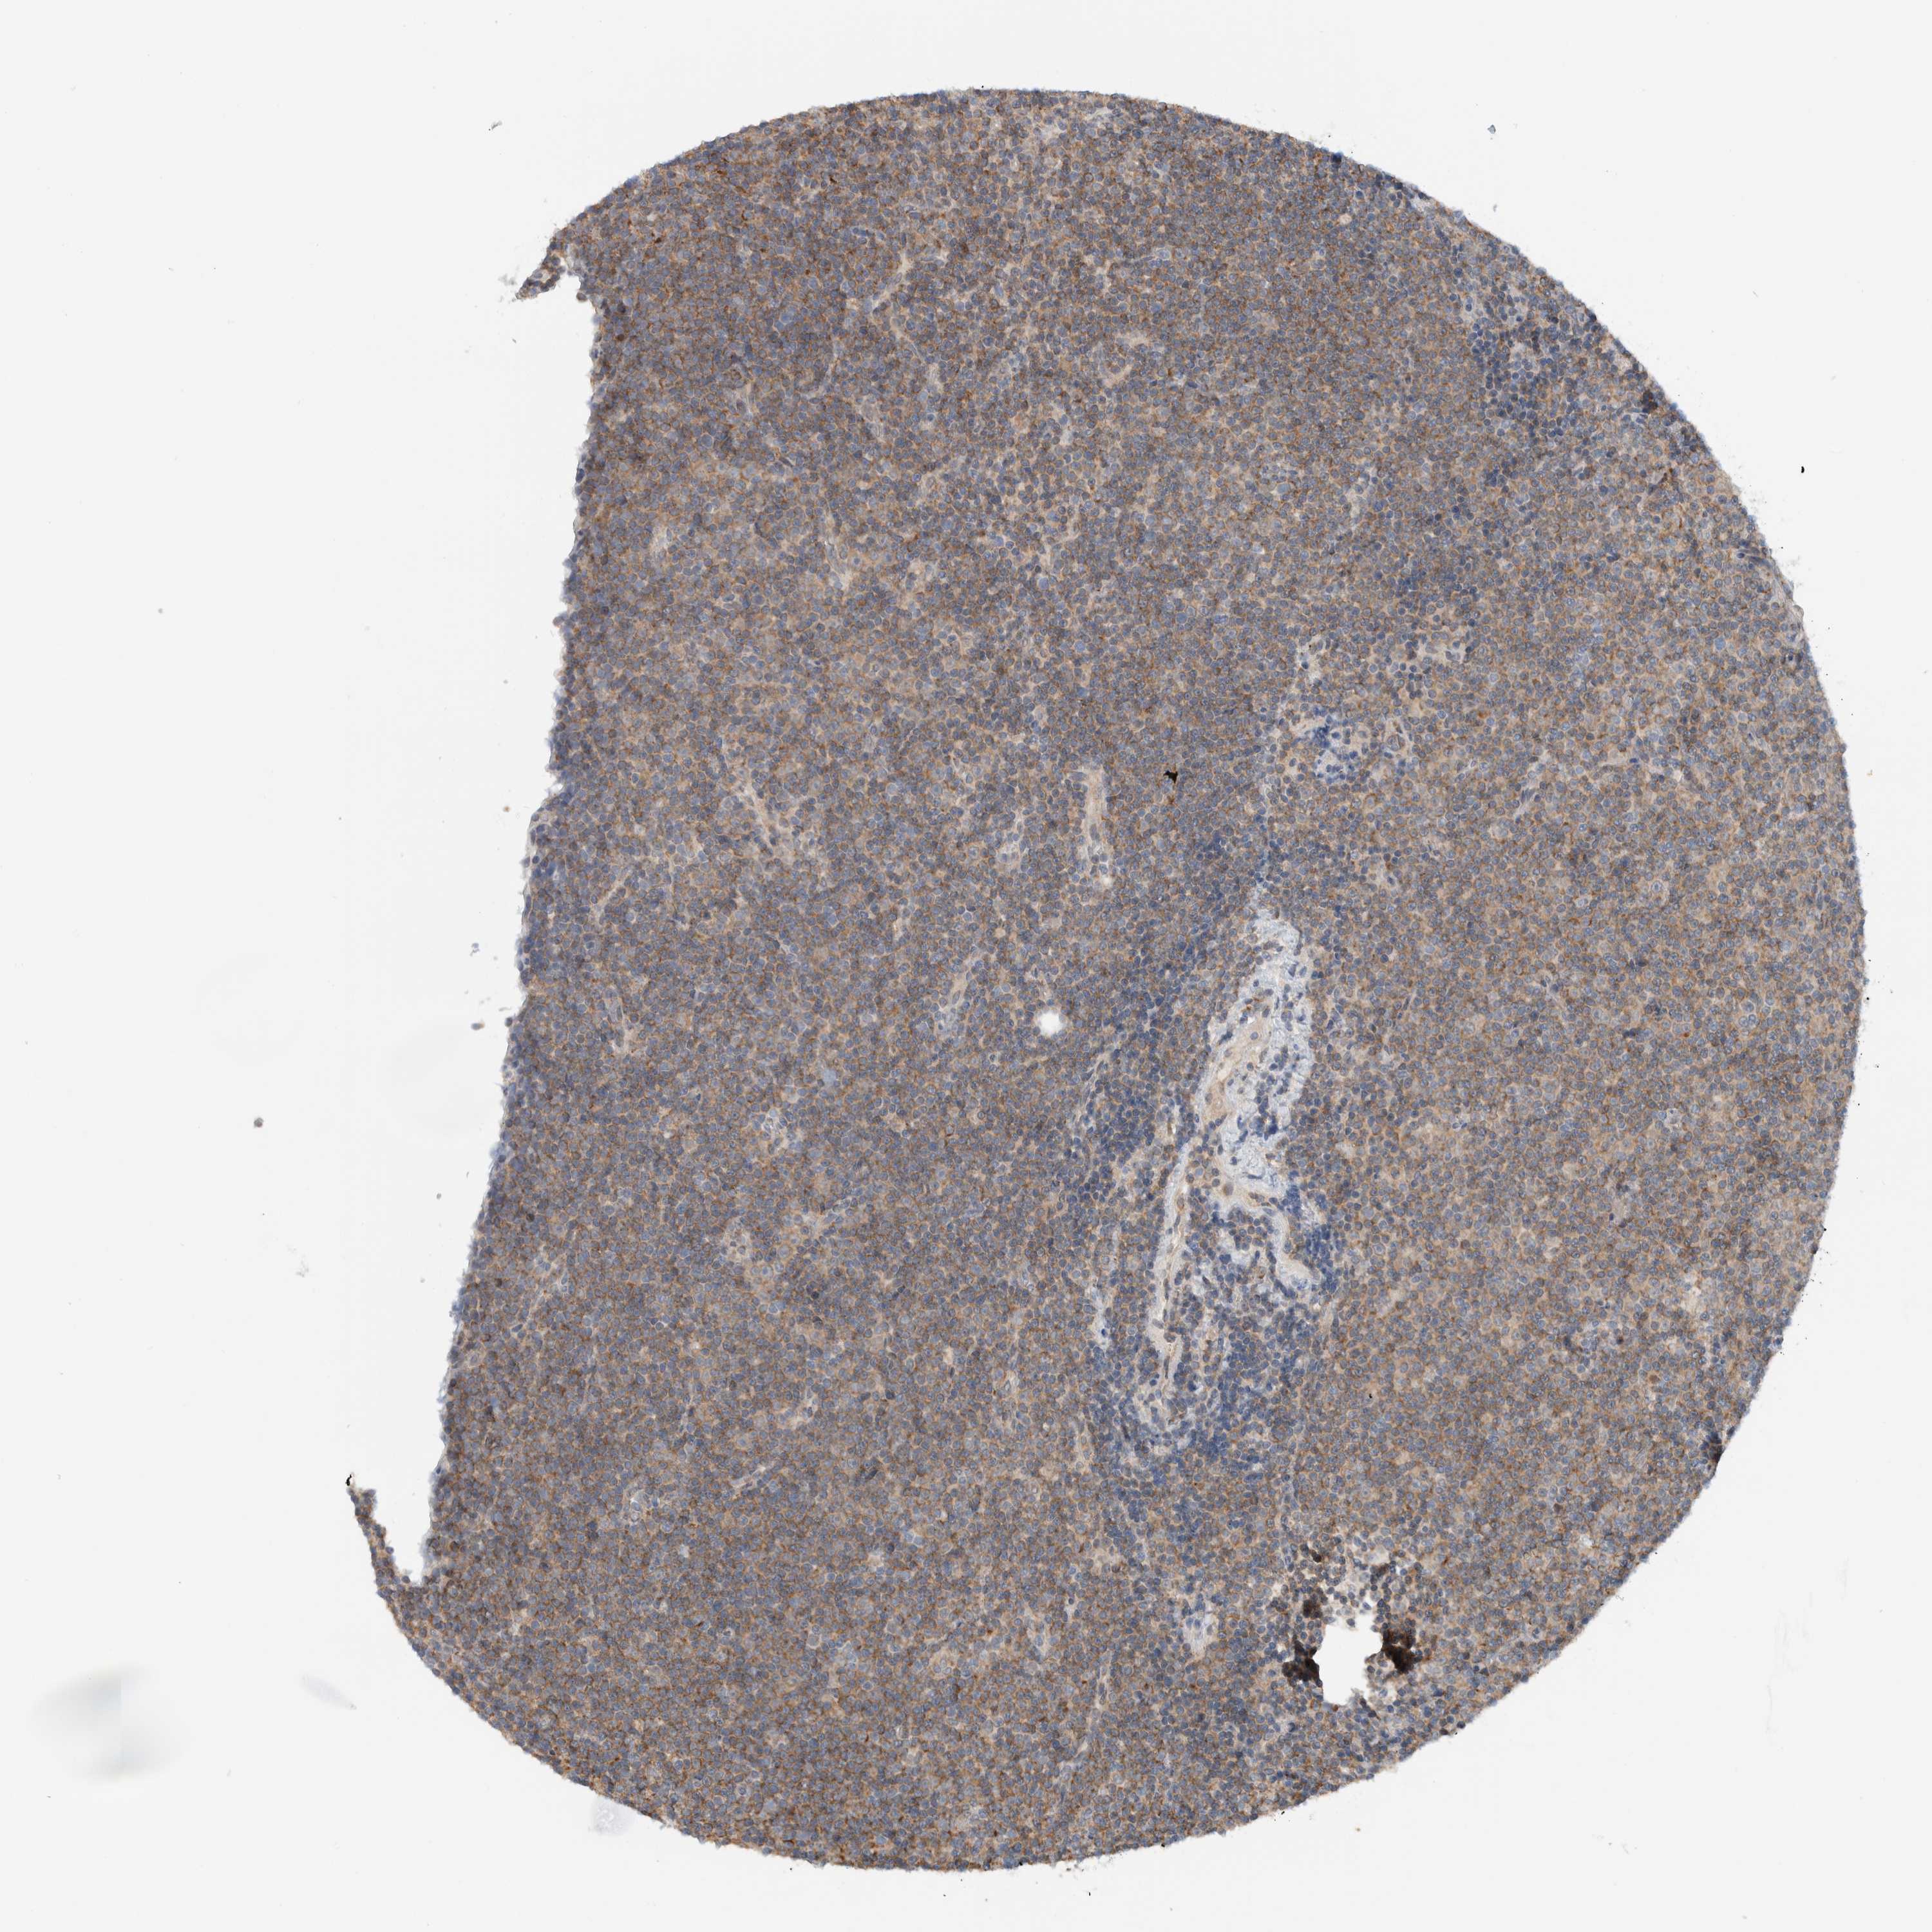

CANCER LYMPHOMA Show tissue menu

LYMPHOMA - Protein expressioni

A mouse-over function shows sample information and annotation data. Click on an image to view it in a full screen mode. Samples can be filtered based on level of antibody staining by selecting one or several of the following categories: high, medium, low and not detected. The assay and annotation is described here.

Each image is clickable and will lead to virtual microscopy that enables deeper exploration of all samples and also displays staining intensity scores, fraction scores and subcellular localization as well as patient and tissue information for each sample.

Antibody HPA024093

Staining

High

Medium

Low

Not detected

Intensity

Strong

Moderate

Weak

Negative

Quantity

>75%

75%-25%

<25%

None

Location

Nuclear

Cytoplasmic/membranous

Cytoplasmic/membranous,nuclear

Hodgkin's disease, NOS

Malignant lymphoma, non-Hodgkin's type, High grade

Malignant lymphoma, non-Hodgkin's type, Low grade